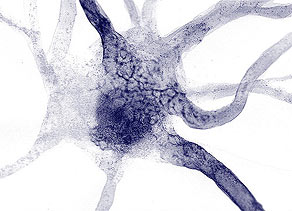

Hogy hat az idegsejtekre?

A mágnesen mezők hatására az idegsejtek ingerületátviteli tulajdonsága

megváltozik, pontosabban csökken az idegsejtek ingerelhetősége. Vagyis

a fájdalom érzékelése és a fájdalom impulzusok agyba történő

továbbítása is csökken.